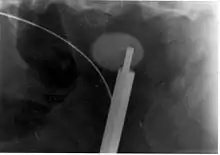

Ureteroscopy has become increasingly popular as flexible and rigid fiberoptic ureteroscopes have become smaller. One ureteroscopic technique involves the placement of a ureteral stent (a small tube extending from the bladder, up the ureter and into the kidney) to provide immediate relief of an obstructed kidney. Stent placement can be useful for saving a kidney at risk for postrenal acute kidney failure due to the increased hydrostatic pressure, swelling and infection (pyelonephritis and pyonephrosis) caused by an obstructing stone. Ureteral stents vary in length from 24 to 30 cm (9.4 to 11.8 in) and most have a shape commonly referred to as a "double-J" or "double pigtail", because of the curl at both ends. They are designed to allow urine to flow past an obstruction in the ureter. They may be retained in the ureter for days to weeks as infections resolve and as stones are dissolved or fragmented by ESWL or by some other treatment. The stents dilate the ureters, which can facilitate instrumentation, and they also provide a clear landmark to aid in the visualization of the ureters and any associated stones on radiographic examinations. The presence of indwelling ureteral stents may cause minimal to moderate discomfort, frequency or urgency incontinence, and infection, which in general resolves on removal. Most ureteral stents can be removed cystoscopically during an office visit under topical anesthesia after resolution of urolithiasis.[114] Research is currently uncertain if placing a temporary stent during ureteroscopy leads to different outcomes than not placing a stent in terms of number of hospital visits for post operative problems, short or long term pain, need for narcotic pain medication, risk of UTI, need for a repeat procedure or narrowing of the ureter from scarring.[115]